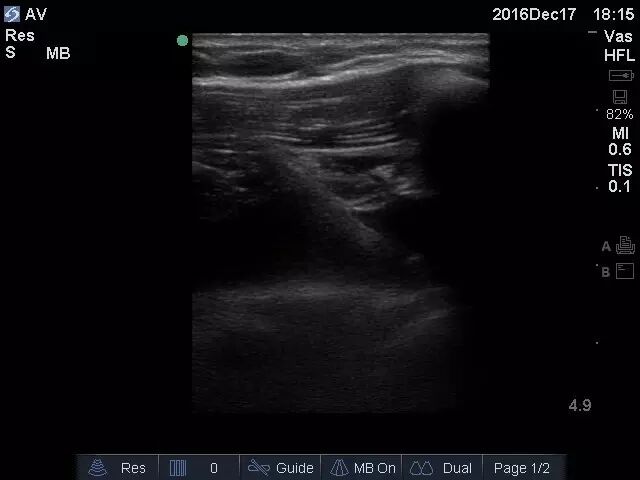

经治疗,患者血压回升,症状好转,意识转清。操作过程中可实时观察穿刺针位置(图3),一次性进入腋静脉,操作过程安全快速(图4)。

图3 采用平面内引导可以观察到穿刺针进入腋静脉全过程